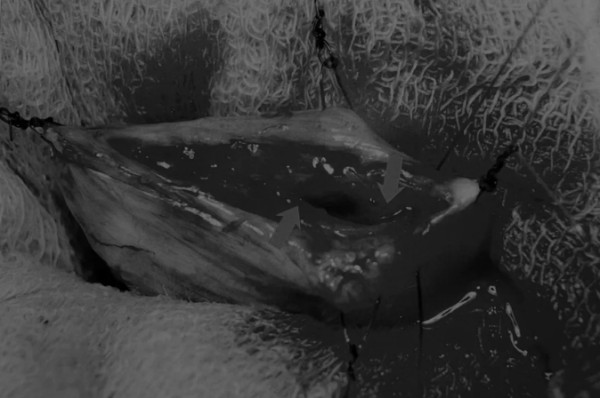

在牵引缝线之间选择血管扩张较差的区域用手术刀切开膀胱壁(图3)。在牵引缝合线之间用手术刀在血管不良的区域做切口。切开膀胱壁后,膀胱内的手术可按手术方案实施,例如取出结石(图4)。

图3 避开主要的膀胱血管,做一个尽可能小的切口